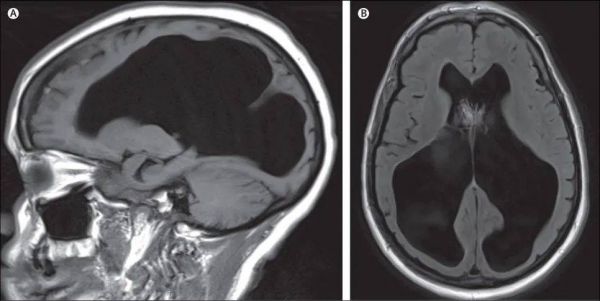

2007年,英国医学权威杂志《柳叶刀》上的病例让世人震惊。这名法国男子44岁,是一名政府公务员。当时,他因为左腿有些毛病才去看的医生。结果医生在为其进行大脑CT和核磁共振扫描后,就惊讶地发现,他的脑室内充满了脑脊液。

那些本该正常的脑组织,则因脑脊液的挤压薄得就像一张纸。脑力测试显示,他的智商为75,虽然比普通人低分略低,但还远不止于被列为智力障碍行列。而且他的生活过得也很美满,几乎没有受影响。事实上,他早已结婚并育有两个孩子,而且还是一位政府公务人员。

2016年,《柳叶刀》发表的一篇论文中,显示了一位62岁的女性患者脑积水的扫描图。该患者(有高血压病史和2型糖尿病)在入院前精神状态一直很好。© The Lancet